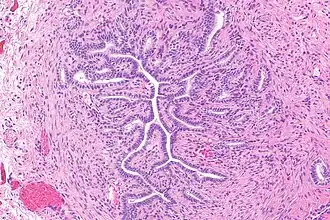

Gartner's duct, also known as Gartner's canal or the ductus longitudinalis epoophori, is a potential embryological remnant in human female development of the mesonephric duct in the development of the urinary and reproductive organs.[2] It was discovered and described in 1822 by Hermann Treschow Gartner.

Gartner's duct is located in the uterus' broad ligament. Its position is parallel with the lateral uterine tube and lateral walls of vagina and cervix.

These may give rise to Gartner's duct cysts.[3]